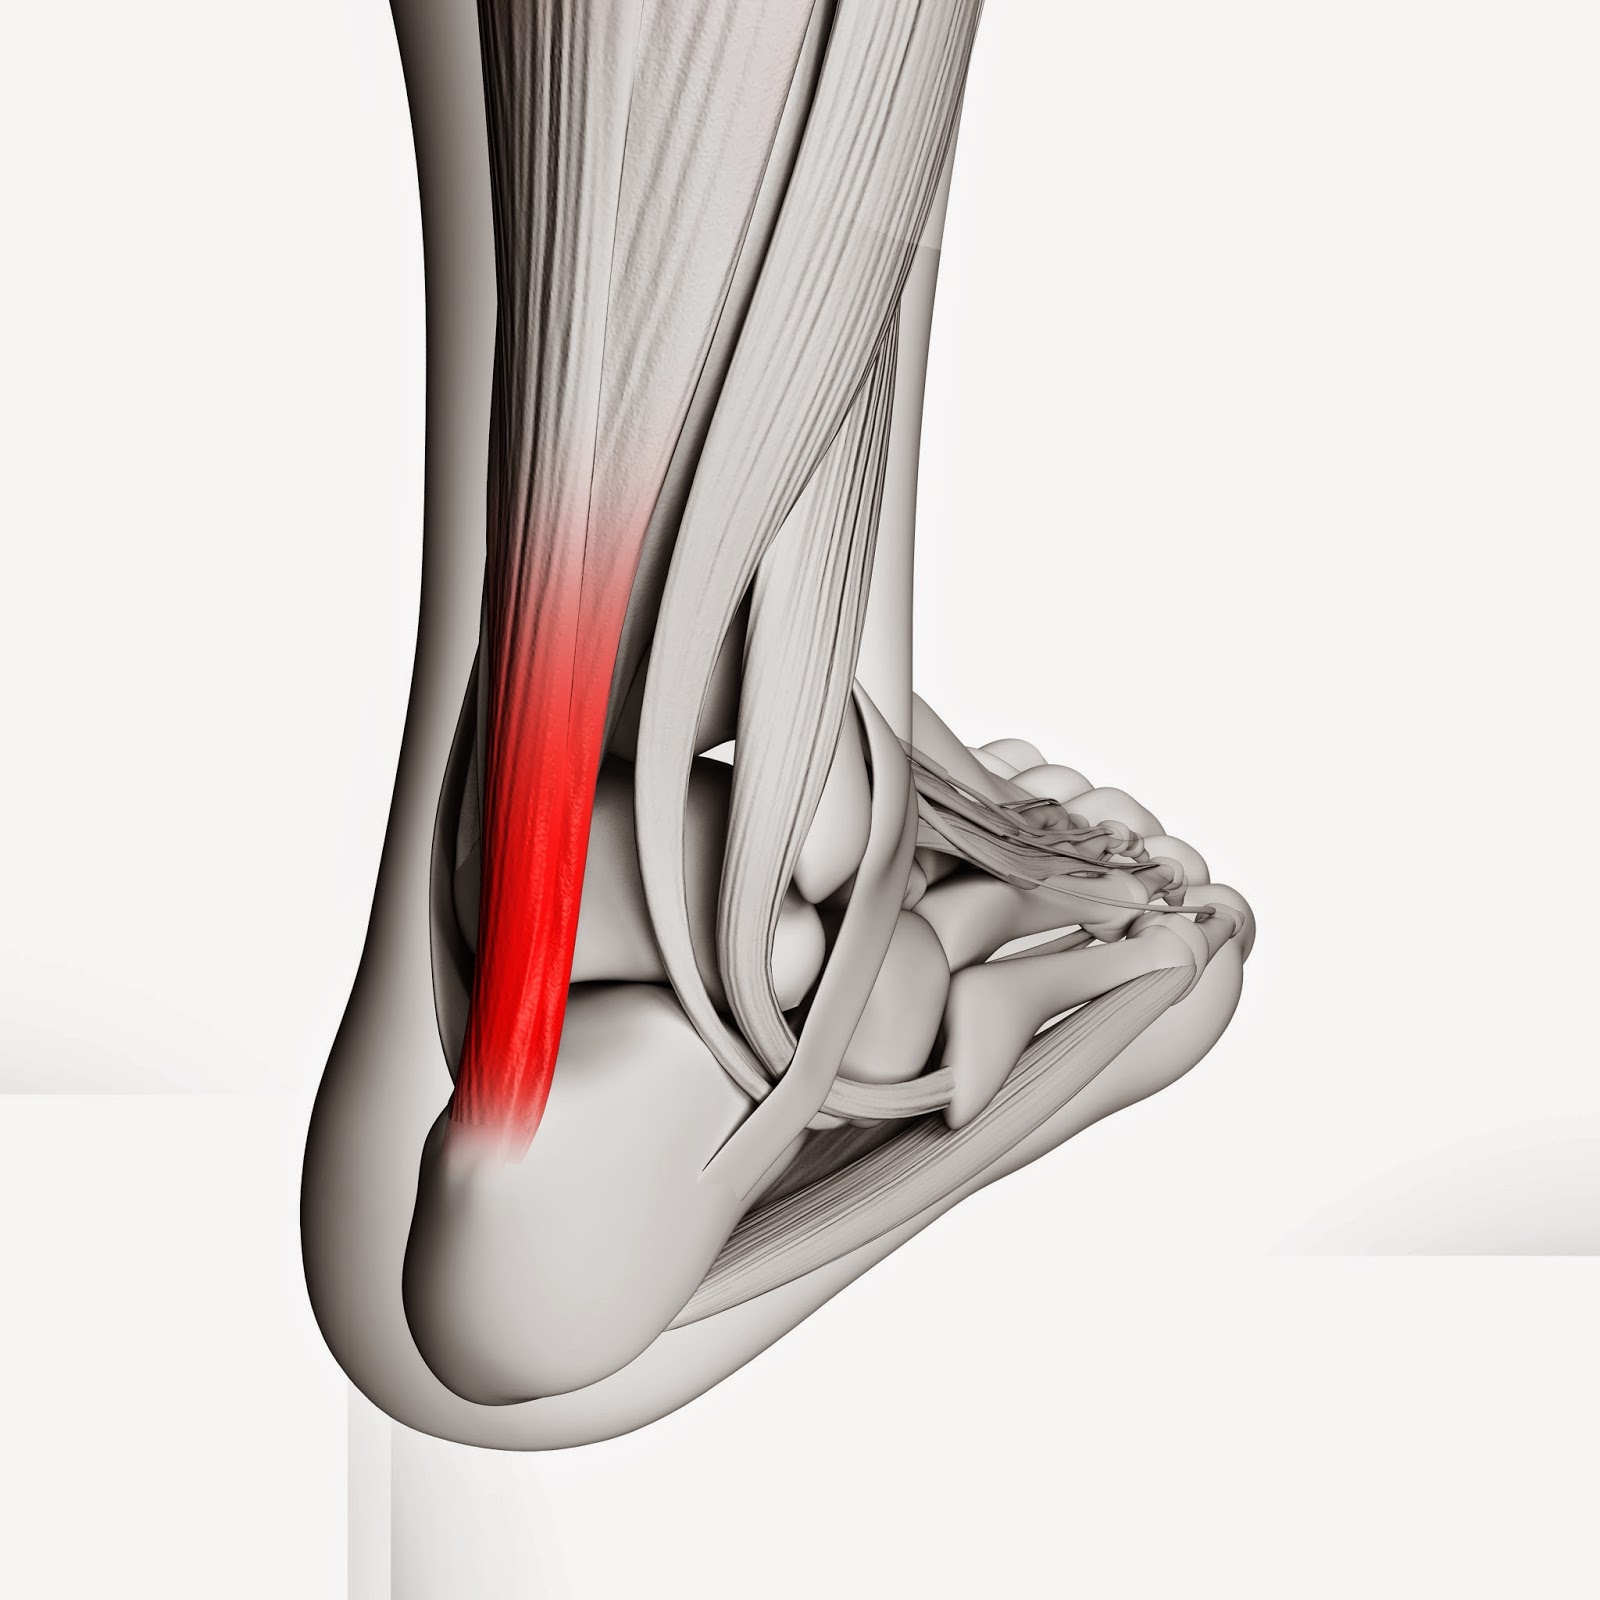

pictures of achilles tendon

Achilles Tendon Injuries – Active Care

Achilles Tendon Pain and Injury

Common Injuries of the Achilles Tendon – Osteopathy Singapore